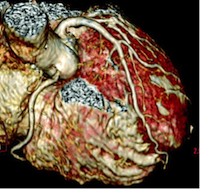

(冠動脈MRI)

呼吸及び心電図同期を併用しながら、冠動脈内の血流信号を画像化します。造影剤を用いることなく冠動脈形態評価が可能であり、また冠動脈石灰化の影響を受けずに検査が可能であることから、 冠動脈CT検査では評価困難な高度石灰化例や呼吸停止困難な症例の検査が可能です。